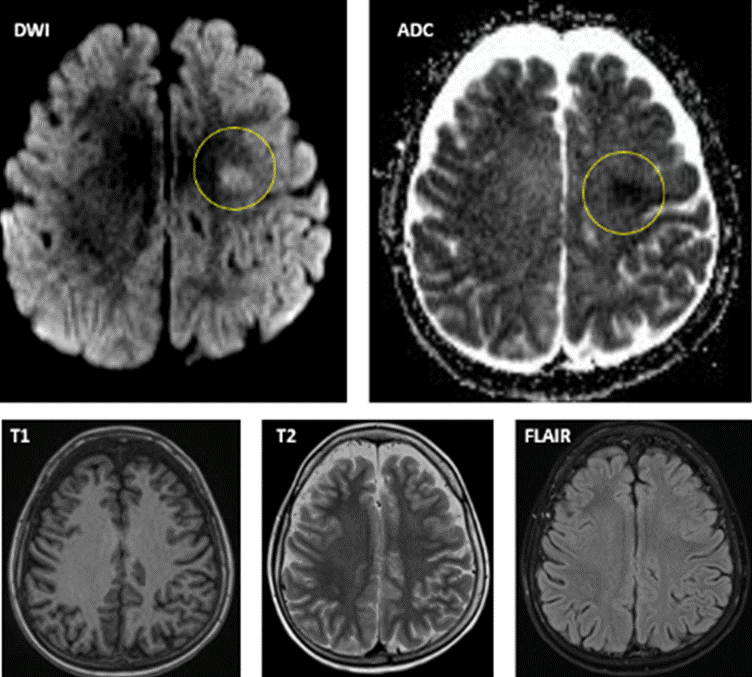

Se solicita resonancia magnética (RMN) de SNC con contraste. En la difusión se observa en sustancia blanca profunda de la circunvolución precentral izquierda, área bien circunscrita de restricción. El mapa ADC muestra la hipointeintensidad correspondiente. Dicho hallazgo carece de expresión en FLAIR. Imágenes compatibles con edema citotóxico por evento isquémico (Figura 1). Se complementa estudio con angioRMN de vasos intracerebrales, cuyo resultado no está disponible en ese momento.

El diagnóstico en fase aguda se realiza con RMN de SNC con difusión(25). Se observa en la sustancia blanca profunda (principalmente frontal y parietal) lesiones evidentes en difusión (edema citotóxico que restringe en difusión) y en el mapa del coeficiente de difusión aparente (ADC), con poca expresión en FLAIR y T2(9,26,27). Las alteraciones observadas en la difusión pueden ser transitorias, por tal motivo una RMN normal no excluye el diagnóstico de neurotoxicidad por MTX(25). La TAC SNC en general no es necesario realizarla, excepto en casos de síntomas sugestivos de sangrado.

Figura 1. RMN de SNC con contraste: en la técnica de difusión se observa en sustancia blanca profunda de la circunvolución pre central izquierda un área bien circunscripta de restricción. El mapa ADC muestra la hipointeintensidad correspondiente. Dicho hallazgo carece de expresión en FLAIR.